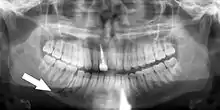

Root fracture

Simple mandible fracture

3D CT of mandible fracture.